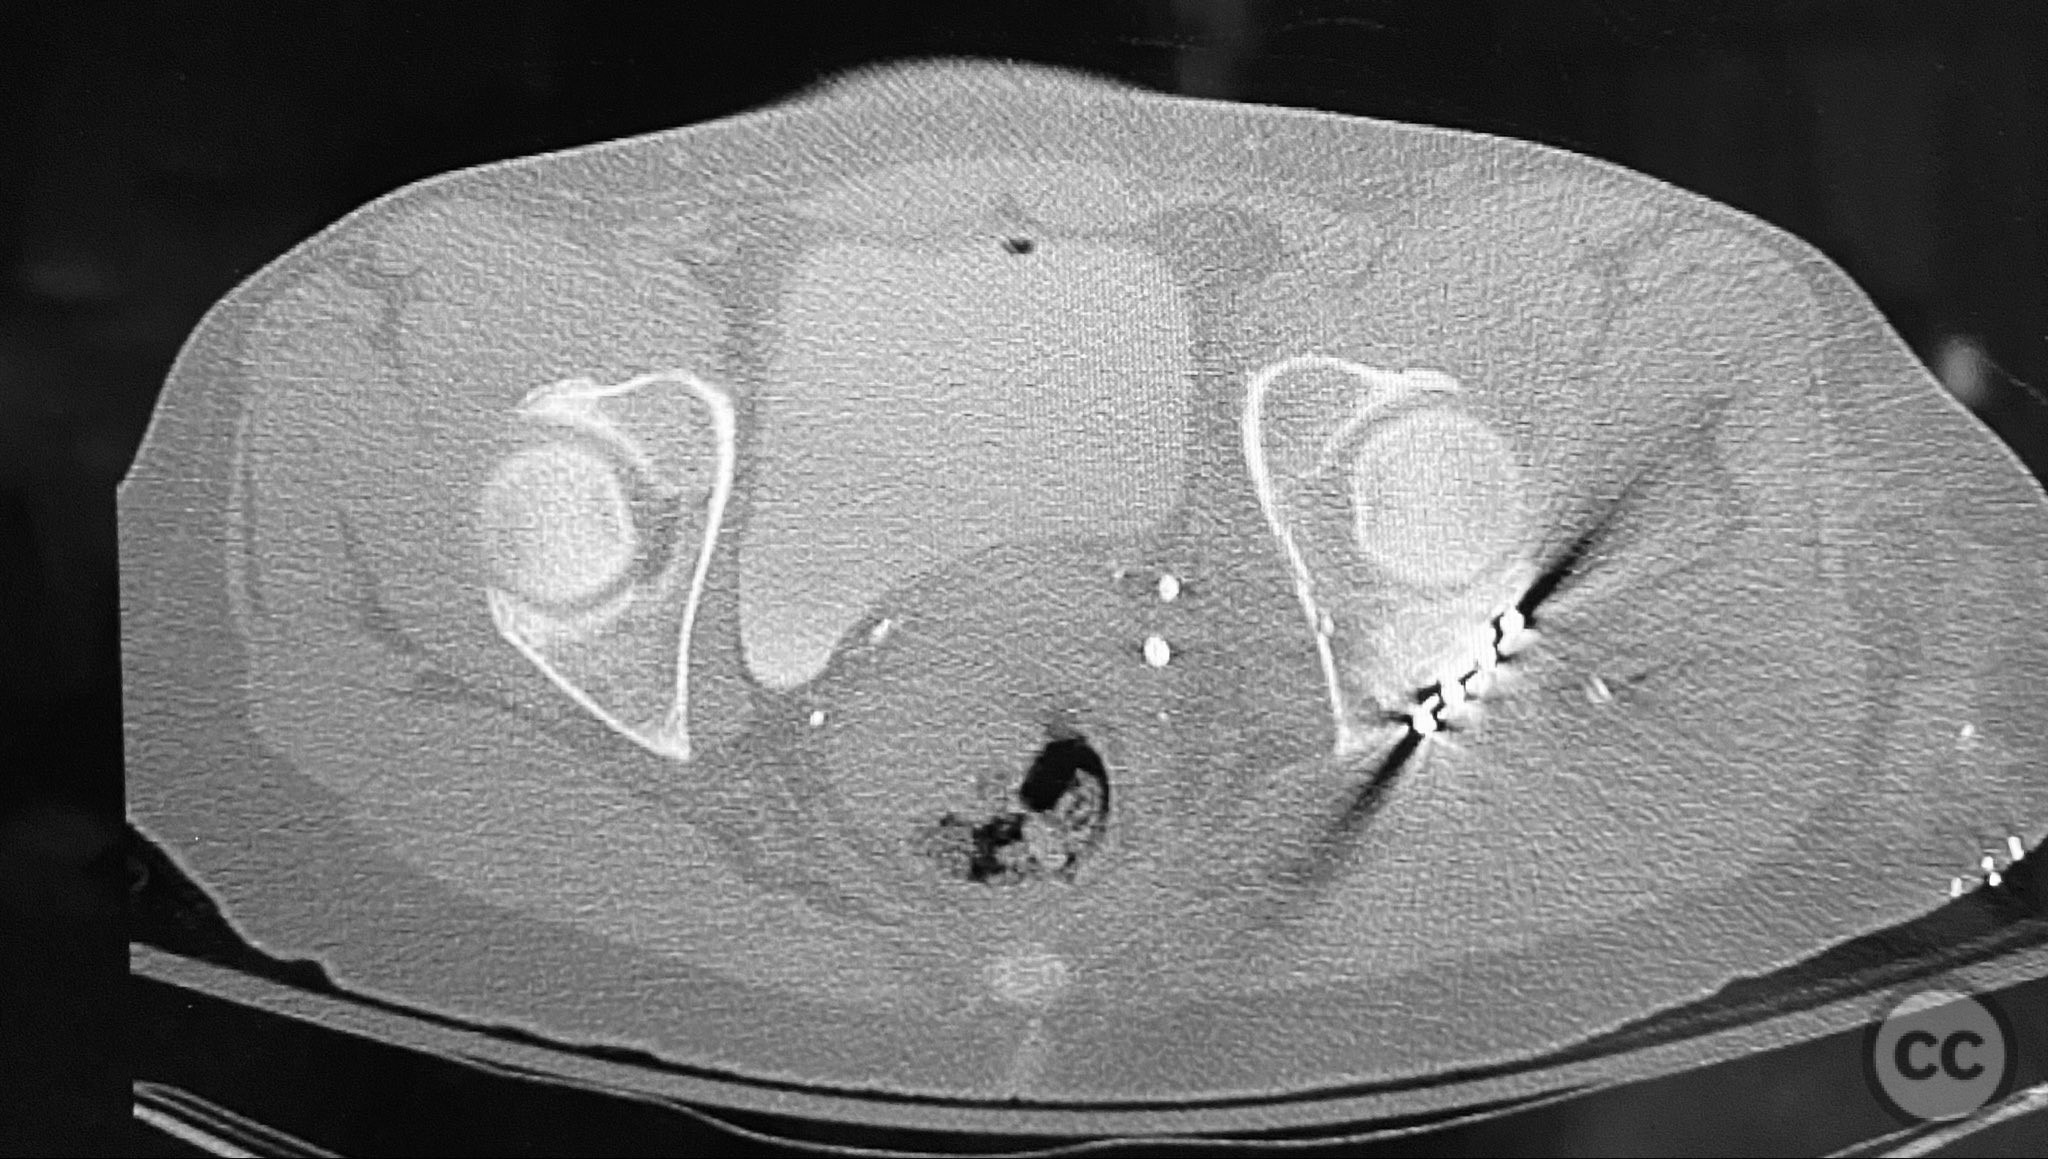

Clinical and radiological findings:  A patient sustained a posterior wall acetabular fracture-dislocation, characterized by comminution of the posterior wall, impaction of fragments into the posterior column region, and intra-articular loose fragments within the fossa acetabuli. Sagittal imaging demonstrated femoral head impalement on the intact wall, raising concern for potential irreducibility. Coronal and axial CT images revealed acetabular and femoral head impactions, peripheral wall comminution, incomplete fracture extension at the acetabular notch and quadrilateral surface, and an articular fragment within the joint. Surface renderings confirmed the extent of peripheral wall comminution and impaction. Despite these findings, a closed manipulative reduction was successfully achieved, resulting in a congruent reduction on post-reduction imaging.

The injury demonstrated extensive comminution and impaction of the posterior wall with intra-articular debris requiring meticulous removal and elevation. The use of a distractor facilitated both exposure and removal of loose articular fragments. The peripheral comminution necessitated augmentation with a custom spring hook plate to maintain reduction of small cortical fragments not amenable to standard buttress plating. Proper placement of the lateral reconstruction plate overlying the spring hook plate was critical for maintaining fixation integrity; malpositioning resulted in early fixation failure in a comparative case due to bending of the unsupported spring hook implant.